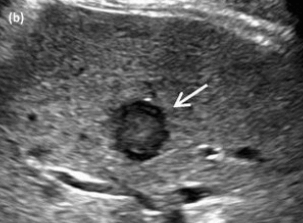

<2cm small hcc sono features ② 2~3cm hcc sono finding

- hypo-hyperechoic

- ireegular margin

- halo(+) 종양이 2cm 이상 커지면 주위조직을 밀게 되면서 피막이 형성되면서 저에코 테두리가 나타남. (간세포암의 40~50%)

감별진단

- metastases

2~3cm hcc sono features ③ 3~5 cm hcc sono finding